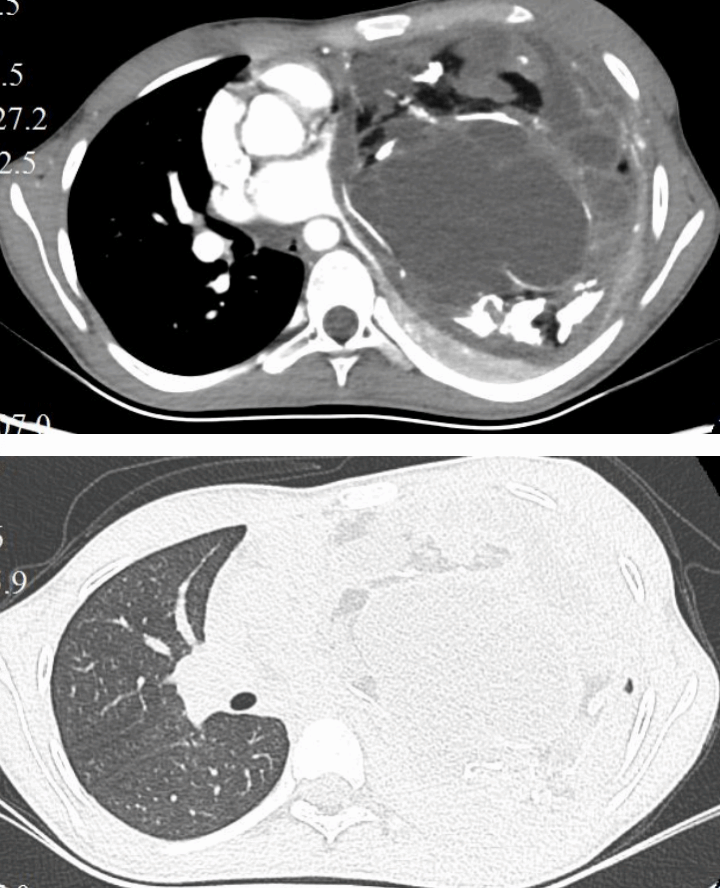

从胸部CT可以更加清晰地看到心脏和大血管受压移位的情况。